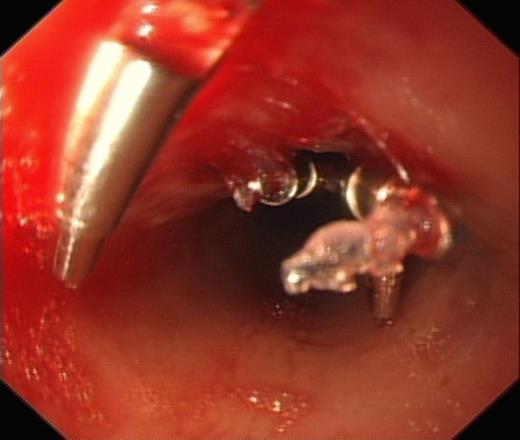

He subsequently underwent an Oesphago-gastro-duodenoscopy (OGD), which showed 2 separate oesophageal perforations, the first at 25cm from the incisors and the second at 27cm from the incisors. The perforation at 25cm was successfully clipped, however the second perforation at 27cm was deemed too big to clip (Fig. 1 & 2).

OGD showing clipped perforation at 25cm from incisors and further perforation at 27cm from incisors